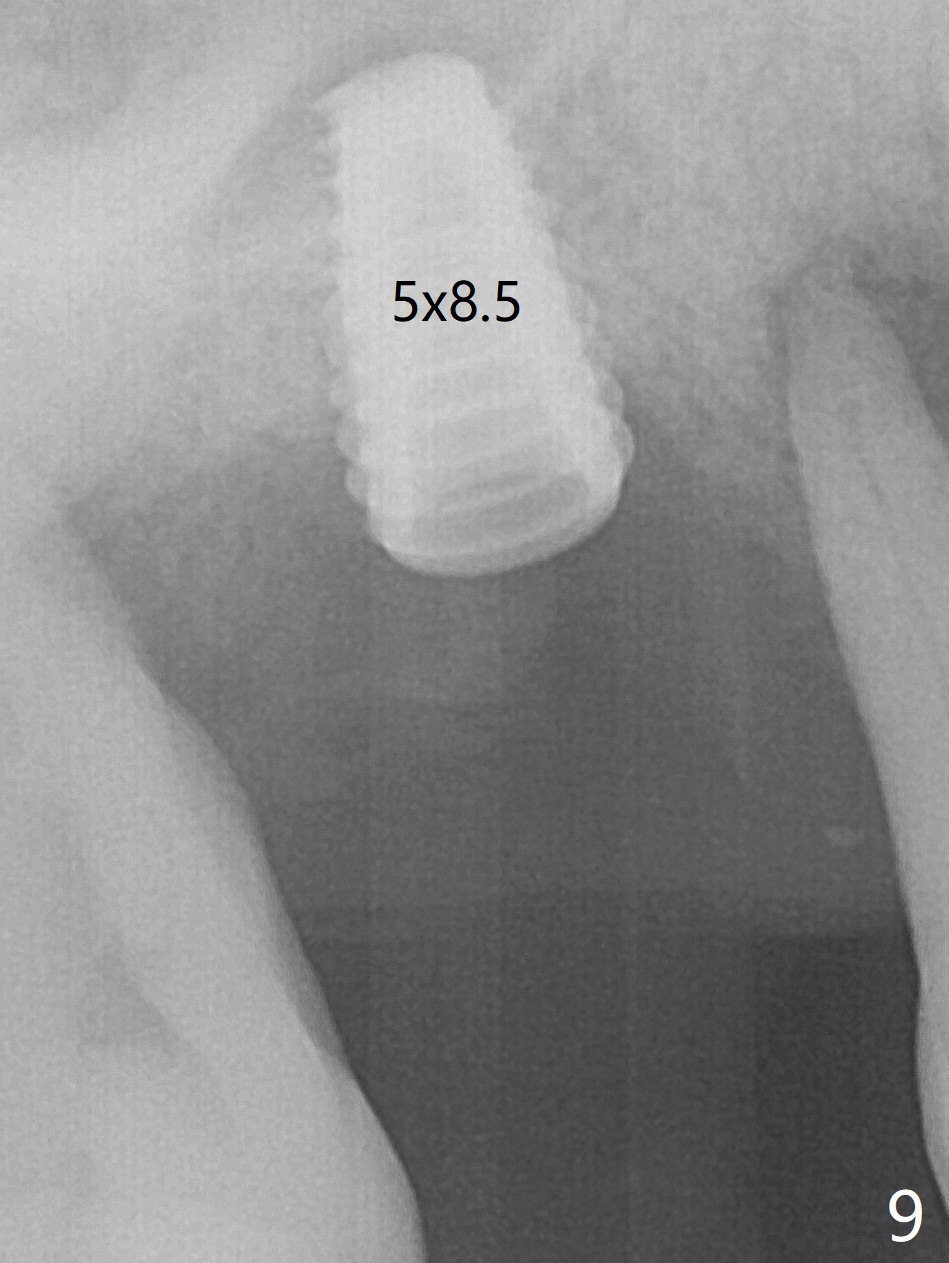

Initial osteotomy depth is 4 mm (Fig.7). The sinus membrane is found to be perforated when the depth increases to 8 mm. The latter could be prevented by taking CT and/or using osteotome. The subsequent osteotomy depth is 5 mm until 4.0 mm in diameter. When the 4.5 mm tap is inserted with initial stability, the shortest implant (8.5 mm, Fig.8 green) will be partially protruded into the sinus and partially exposed in the socket and the cuff of the abutment is expected to be around 6 mm (pink). Since the 5 mm tap achieves primary stability, a 5x8.5 mm implant (following placement of Osteogen plug to repair the perforated sinus membrane) is placed at the level just mentioned (Fig.9). Vanilla Graft mixed with minimal autogenous bone is packed (Fig.10.11 *) before and after insertion of a 6.5x5(4) mm abutment. An immediate provisional as well as a piece of Osteogen plug is fabricated to close the socket gap. The provisional and the abutment are dislodged 1 month postop (Fig.12). The wound has healed. The abutment is reloaded without the provisional. The implant appears to osteointegrate 4.5 months postop (Fig.13); in addition the bone graft seems to have migrated toward the roots of the neighboring teeth (arrows).